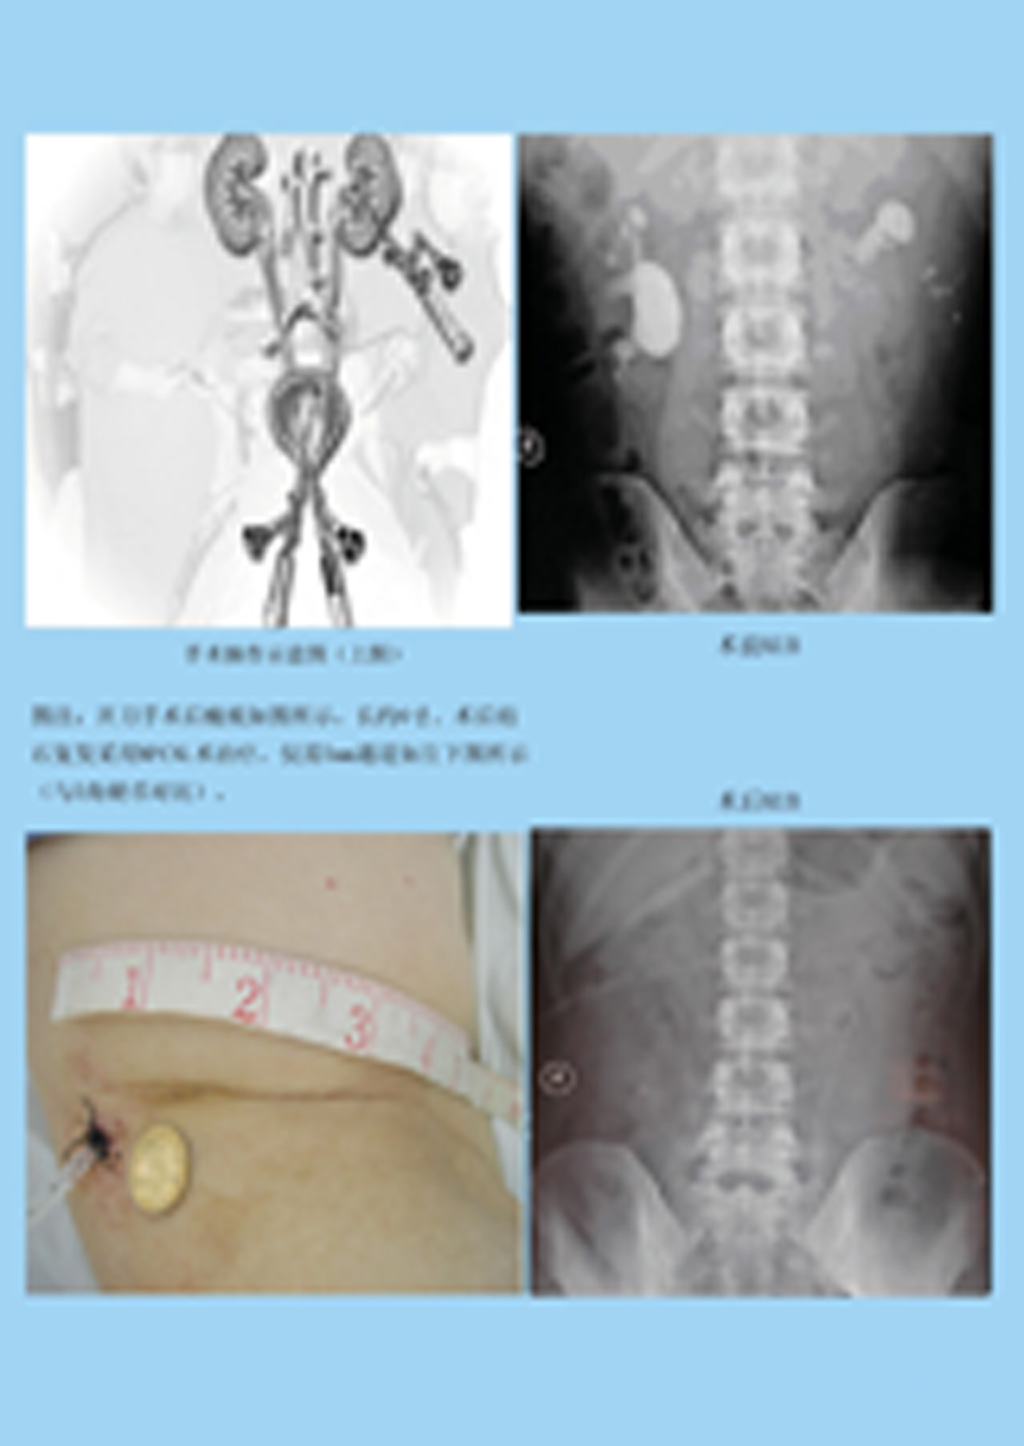

【微创经皮肾镜碎石取石术】

在B超或C型臂X线结合引导下,在腰部打一个5毫米大小的小孔,建立起皮肤至肾脏的通道,在经皮肾镜引导下结石显示于显示屏上采用钬激光或气压弹道对准结石,将结石瞬间汽化或粉碎为粉沫状,应用清石系统将粉沫结石吸出体外,又称为‘打洞取石’。

优势:不开刀、微创伤、痛苦小、出血少、恢复快、费用低、大大缩短住院时间,通常5-7天即可出院。

适应症:主要治疗疑难的巨大肾结石、多发肾结石、鹿角型肾结石、输尿管上段结石。